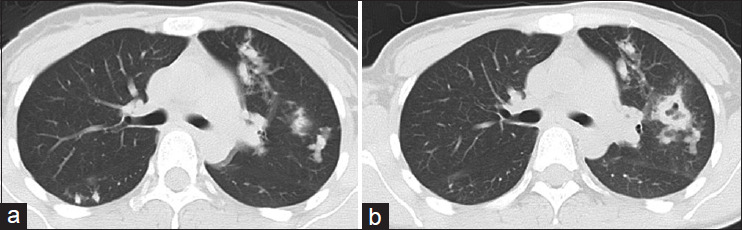

A 32-year-old Chinese woman with a cough and bloody sputum was diagnosed with chronic eosinophilic pneumonia. After starting corticosteroid therapy, chest radiography showed improvement in the bilateral infiltrative shadow. However, chest image findings showed worsening of the bilateral infiltrative shadow and pulmonary cavities during the 20 mg/day of oral prednisolone therapy. Transbronchial lung biopsy and bronchoalveolar lavage were repeated, and the patient was diagnosed with pulmonary paragonimiasis. After starting praziquantel treatment, chest radiography findings and clinical symptoms improved. Careful follow-up during corticosteroid therapy is important to judge whether transient improvement and true deterioration of radiological findings.

一名32岁中国女性因咳嗽和痰血被诊断为慢性嗜酸性粒细胞性肺炎。开始皮质类固醇治疗后,胸片显示双侧浸润影改善。然而,在口服强的松龙20mg /d治疗期间,胸部图像显示双侧浸润阴影和肺腔恶化。经支气管肺活检及支气管肺泡灌洗,诊断为肺吸虫病。开始吡喹酮治疗后,胸片表现和临床症状均有所改善。在皮质类固醇治疗期间的仔细随访对于判断放射学表现是否有短暂改善和真正恶化是很重要的。